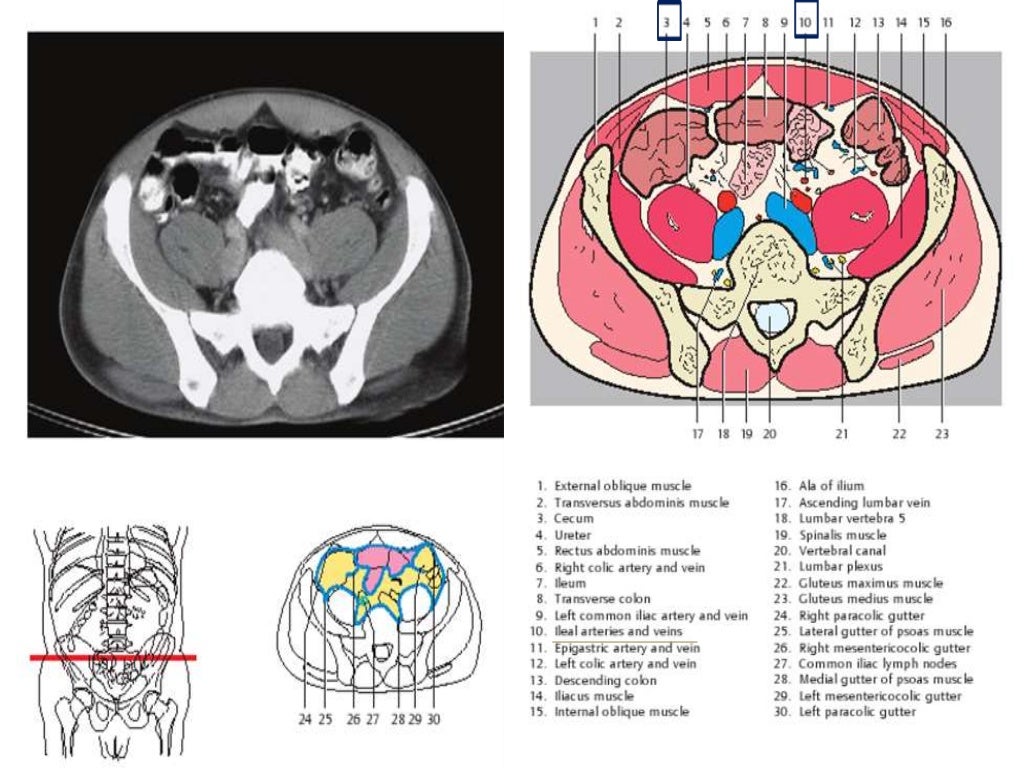

Sectional Anatomy Of Abdomen